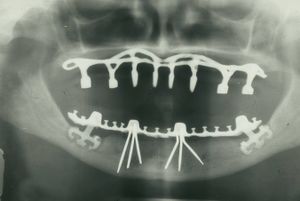

Panoramic radiograph of historic dental implants, taken 1978